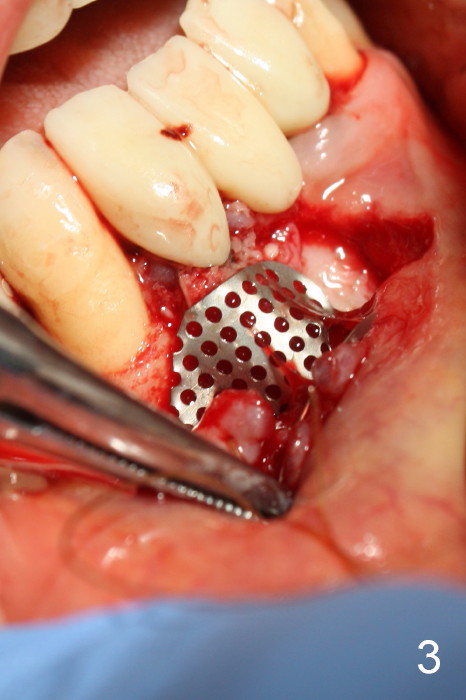

The patient has had chronic pain and swelling associated with the implant at the site of #26 (Fig.1). The extent of implant thread exposure is shown in Fig.2 after flap reflection; inflammatory granulation tissue is present around the most coronal threads (*, one year post cementation). Following debridement and Clindamycin soaking, allograft is placed around the exposed threads; a titanium mesh is used to contain the graft (Fig.3). The flap is closed with tension in spite of the periosteum being underscored. The patient develops moderate to severe ecchymosis postop.